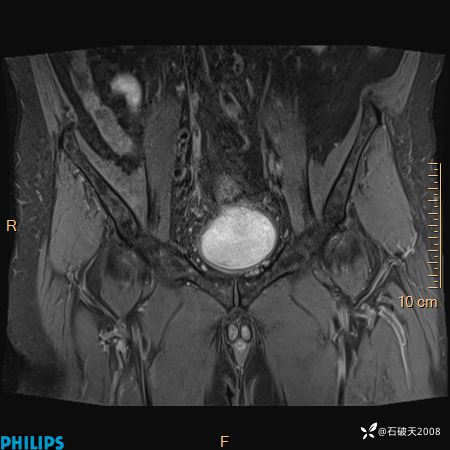

2023年3月份MRI影像

T2压脂冠状位